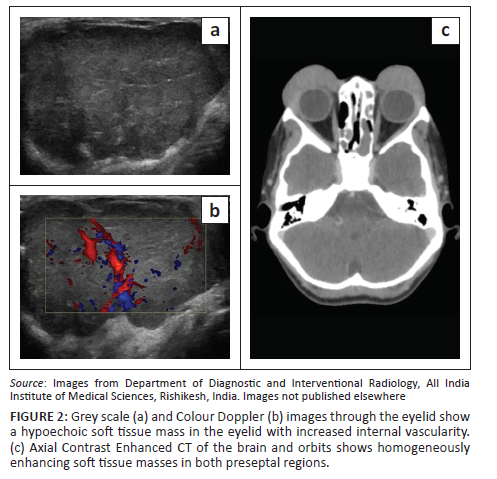

Initial investigation was with ultrasonography (USG) of the cheek and neck (GE Logiq S8, USA), which revealed diffuse enlargement of both parotid and submandibular glands. Multiple enlarged hypoechoic lymph nodes with a lobulated outline, increased vascularity and loss of fatty hila were noted at the parotid, submental and submandibular stations bilaterally. On ultrasound elastography, the lymph nodes showed an intermediate elasticity score (Figure 1). Ocular USG showed hypoechoic soft tissue with marked internal vascularity in both upper eyelids in the preseptal regions (Figure 2a, b). Both the eye globes were unremarkable. Her chest radiograph appeared normal.

A contrast-enhanced (CE) CT scan of the face and neck (Philips Ingenuity Core 64 slice CT) was performed. Homogeneously enhancing soft tissue masses were seen in the preseptal regions of the eyelids (Figure 2c). Multiple enlarged homogeneously enhancing bilateral cervical and parotid lymph nodes were seen (Figure 3a-d).